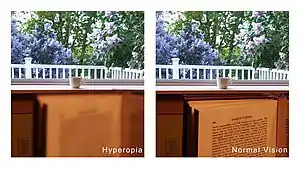

Far-sightedness, also known as long-sightedness, hypermetropia, and hyperopia, is a condition of the eye where distant objects are seen clearly but near objects appear blurred. This blur is due to incoming light being focused behind, instead of on, the retina due to insufficient accommodation by the lens.[6] Minor hypermetropia in young patients is usually corrected by their accommodation, without any defects in vision.[2] But, due to this accommodative effort for distant vision, people may complain of eye strain during prolonged reading.[2][7] If the hypermetropia is high, there will be defective vision for both distance and near.[2] People may also experience accommodative dysfunction, binocular dysfunction, amblyopia, and strabismus.[3] Newborns are almost invariably hypermetropic, but it gradually decreases as the newborn gets older.[6]

In young patients, mild hypermetropia may not produce any symptoms.[2] The signs and symptoms of far-sightedness include blurry vision, frontal or fronto temporal headaches, eye strain, tiredness of eyes etc.[2] The common symptom is eye strain. Difficulty seeing with both eyes (binocular vision) may occur, as well as difficulty with depth perception.[1] The asthenopic symptoms and near blur are usually seen after close work, especially in the evening or night.[6]

In severe cases of hyperopia from birth, the brain has difficulty in merging the images that each individual eye sees. This is because the images the brain receives from each eye are always blurred. A child with severe hyperopia can never see objects in detail. If the brain never learns to see objects in detail, then there is a high chance of one eye becoming dominant. The result is that the brain will block the impulses of the non-dominant eye. In contrast, the child with myopia can see objects close to the eye in detail and does learn at an early age to see objects in detail.